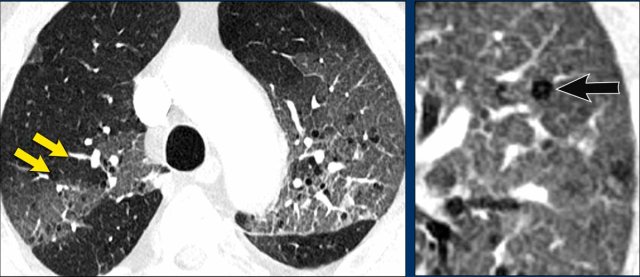

These images are of a 66-year-old man, who is a smoker and complaints of dyspnoe.

Study the image.

What is the most characteristic finding?

What is the most likely diagnosis?

Findings

There are multiple cysts.

Some are irregularly shaped and some have a cheerio sign as a result of cavitation within the nodule (white arrows)

There are also some nodules (black arrows).

Discussion

The combination of these findings in a smoker is typical for the diagnosis LCH.

Continue...

On the coronal reconstruction it is obvious, that the cysts predominantly involve the upper and middle lobes and spare the lung bases.

Especially when LCH is still in the nodular phase, this distribution can be a helpful sign in the differentiation of metastases, which have a lower lobe preference.

This is a similar case.

Notice that the cysts predominantly involve the upper and middle lobes.

The pleural recesses are preserved.

The cysts have caused a pneumothorax.